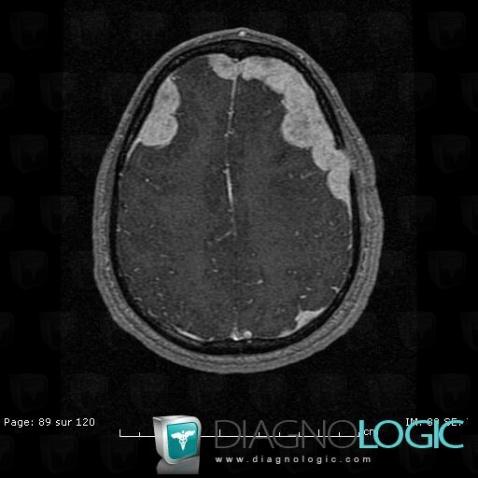

Langerhans cell histiocytosis, Cortico subcortical region, MRI

Here is the specific information in the key image above:

- Diagnosis Langerhans cell histiocytosis, Location(s) Cortico subcortical region, with gamuts Diffuse meningeal enhancement